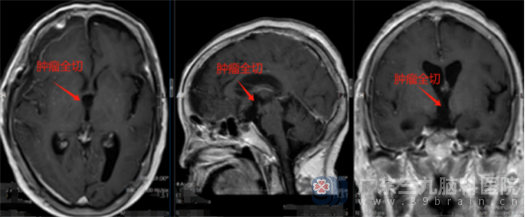

征得患者及家属同意后,鲁明带领神经外五科团队在全麻下为患者行右侧翼点终板入路肿瘤切除术。显微镜下见肿瘤组织呈灰白色,血供一般,质地一般,有胆固醇结晶形成,医生沿肿瘤边界给予分块切除,患者的视神经、垂体柄、双侧下丘脑保护良好,手术顺利完成。

术后,谢奶奶神志清醒。经过预防感染及癫痫、止血、营养神经、护胃、对症及支持等治疗,谢奶奶的情况一天比一天好,很快就顺利出院。术后病理结果诊断为造釉细胞型颅咽管瘤,CNS WHO I级。